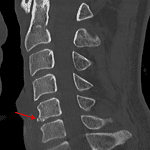

- Acute minimally displaced fracture of the anterior inferior corner of the C5 vertebral body

Acute minimally displaced fracture of the anterior inferior corner of the C5 vertebral body (teardrop fracture).

No traumatic malalignment. MRI could further assess for ligamentous injury if there is clinical concern.